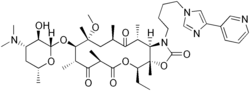

Ketolides are antibiotics belonging to the macrolide group. Ketolides are derived from erythromycin by substituting the cladinose sugar with a keto-group and attaching a cyclic carbamate group in the lactone ring.[1] These modifications give ketolides much broader spectrum than other macrolides. Moreover, ketolides are effective against macrolide-resistant bacteria, due to their ability to bind at two sites at the bacterial ribosome as well as having a structural modification that makes them poor substrates for efflux-pump mediated resistance.[2]

The only ketolide on the market at this moment is telithromycin, which is sold under the brand name of Ketek. Other ketolides in development include cethromycin and solithromycin.